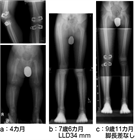

1. 小学校就学前に3㎝程度の脚長差が発生する可能性が高い患児は創外固定器による脚延長を行い、延長側を1㎝程度余分に行い就学前に治療を終了する。その後脚長差が再発した場合は第2次成長期に8 plateによる成長抑制術を行うように計画することが最も負担が少ない治療法である。

1. 先天異常等で幼児期から脚長差の強い患児は3歳を過ぎたぐらいから脚長不当にたいする治療を検討するが、幼児期の大腿延長は、膝蓋骨の大腿膝蓋関節が未成熟で膝蓋骨脱臼を惹起することがあり、注意を要する。